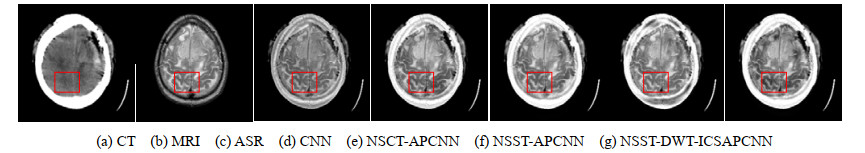

• 摘要: 为了增加融合图像的信息量,结合非下采样剪切波变换(Non-Subsampled Shearlet Transform, NSST)和离散小波变换(Discrete Wavelet Transform, DWT)的互补优势,提出了改进的多模态图像融合方法。采用NSST对两幅源图像进行多尺度、多方向的分解,得到相应的高频子带和低频子带;利用DWT将低频子带进一步分解为低频能量子带和低频细节子带,并利用最大值选择规则融合能量子带;采用改进连接强度的自适应脉冲耦合神经网络(Improved Connection Strength Adaptive Pulse Coupled Neural Network, ICSAPCNN)分别融合细节子带和高频子带,并对能量子带和细节子带进行DWT逆变换,得到融合的低频子带;采用NSST逆变换重构出细节信息丰富的融合图像。实验证明,提出的算法在主观视觉和客观评价方面均优于其他几种算法,且能同时适用于红外与可见光源图像、医学源图像的融合。

Abstract: To increase the information of the fused image, this paper proposes an improved multi-modality image fusion algorithm that combines the complementary advantages of the non-subsampled shearlet transform (NSST) and discrete wavelet transform (DWT). NSST was used to decompose the two source images in multiscale and multi-direction to obtain the corresponding high-frequency and low-frequency sub-bands. The low-frequency sub-bands were further decomposed into low-frequency energy sub-bands and low-frequency detail sub-bands by the DWT, and the low-frequency energy sub-bands were fused by the maximum selection rules. An adaptive pulse-coupled neural network with improved connection strength (ICSAPCNN) was used to fuse the detailed sub-bands and high-frequency sub-bands, and the energy sub-bands and detailed sub-bands were fused by inverse DWT to obtain the fused low-frequency sub-bands. The NSST inverse transform was used to reconstruct the fusion image with rich details. The experimental results verified that the proposed algorithm is superior to the other algorithms in both subjective vision and objective evaluation and can be applied to the fusion of both infrared and visible source images and medical source images.